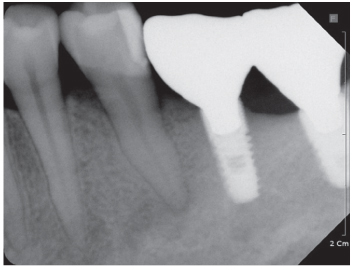

Figure 3

Periapical view taken 2 years ago.

Figure 3 Periapical view taken 2 years ago.